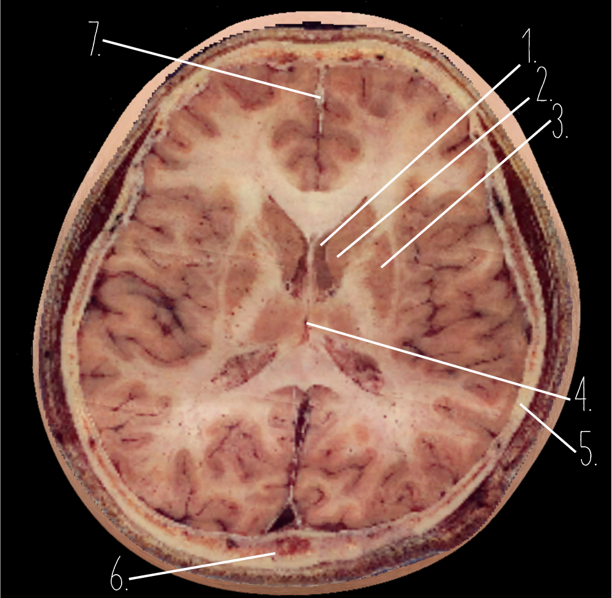

Brain Cross Sectional

1?

Anterior Horn of the Lateral Ventricle

2?

Putamen

3?

Thalamus

4?

Internal Occipital Protuberance

5?

Cerebellar Vermis

6?

Third Ventricle